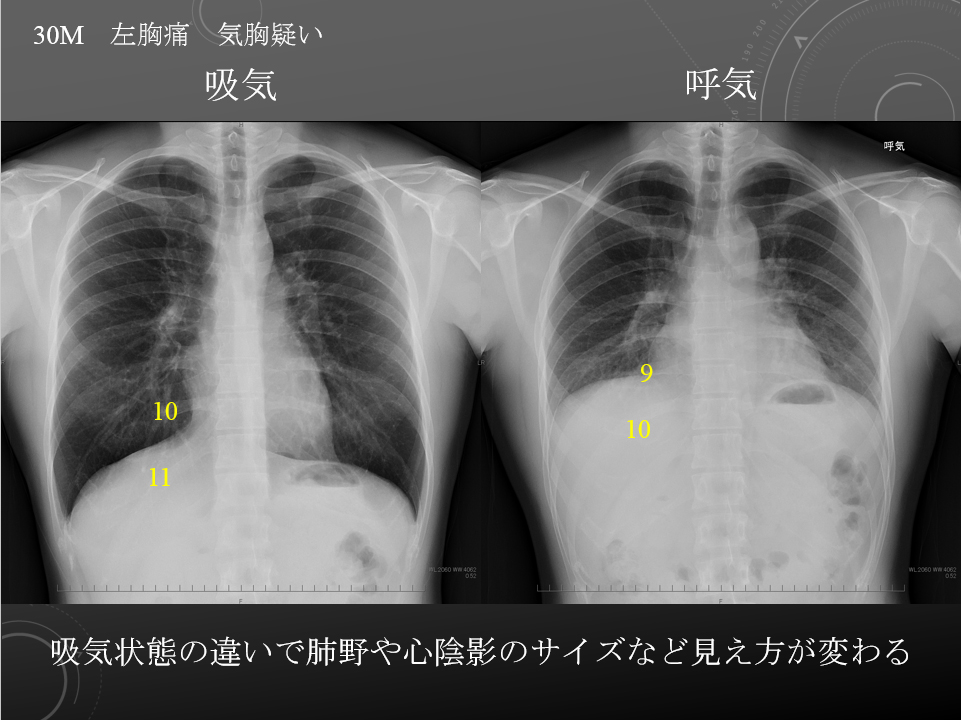

30M 血小板減少症 左胸痛 気胸疑い

胸部:吸気/呼気、側面